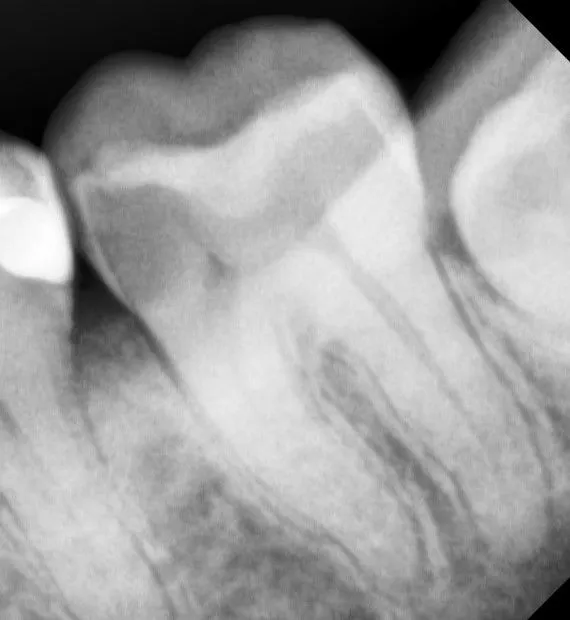

Пациент, 33 года обратился с жалобами на ноющую боль слева снизу.

Провели лечение корневых каналов и подготовили зуб под коронку.